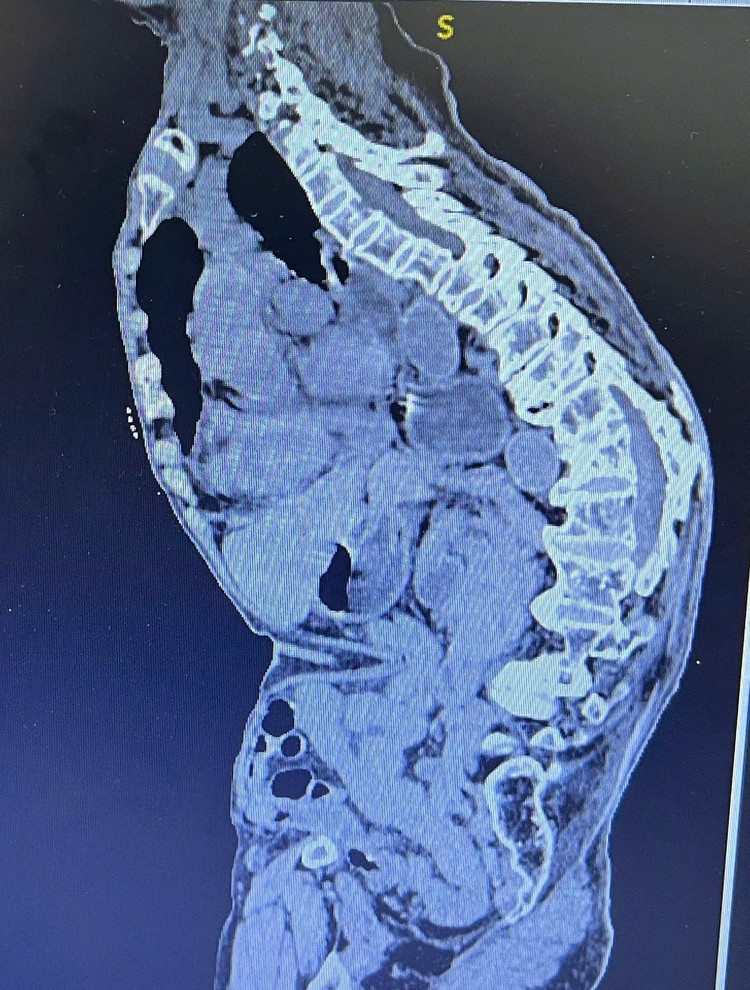

Bệnh nhân thể trạng gầy yếu, chỉ cao khoảng 1,4 m và nặng 32 kg. Bà bị gù vẹo cột sống nặng do tiền sử chấn thương cột sống, với độ gù khoảng 60 độ, nên gặp nhiều khó khăn trong việc đi lại và sinh hoạt hàng ngày.

| Hình ảnh phim chụp bệnh nhân bị gù vẹo cột sống nặng - Ảnh BSCC |